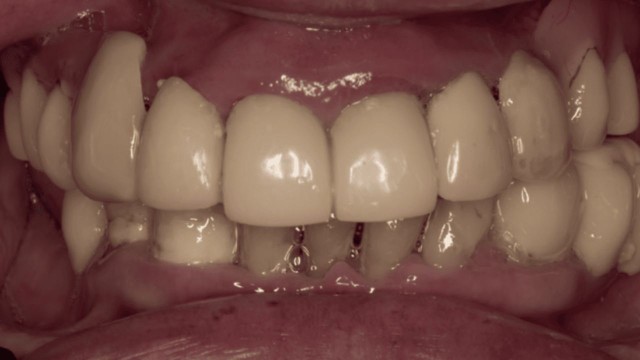

Situazione intra-orale della paziente. Nell’arcata superiore è presente uno scheletrato con attacchi e nell’arcata inferiore corone provvisorie nei settori posteriori. E’ ben evidente sia il difetto estetico che quello funzionale con alterazione dei piani occlusali in entrambe le arcate.

Sorriso della paziente con le attuali riabilitazioni. La richiesta della stessa è quella di risolvere la situazione sia funzionale che estetica senza il ricorso all’ausilio di protesi rimovibili. Si decide quindi in accordo con la paziente di eseguire 2 riabilitazioni implanto-supportate secondo la metodica all-on-4 ®.